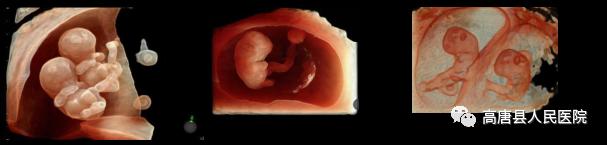

超越GE传统的HDlive成像模式,借助强大的GPU的处理能力,增加了组织透明度调节,实现100级可调,从内到外,一览无余。带来容积图像更强的边界感与距离感。煊影成像技术在早孕、双胎等评估有良好优势。

独有的煊影成像(HDlive Silhouette)和煊流技术(HDlive Flow),给容积超声带来出色的分辨率。胎儿识别追踪技术(SonoRenderlive)简化了胎儿表面成像,对于早孕的评估极有优势。

产科领域:具有2D-4D的优良图像质量,可以实时立体直观动态地检测胎儿,具有排查胎儿畸形准确,照片清晰的特点。对于11-14周胎儿NT值测量、中晚期胎儿的排畸筛查更准确性,尤其针对唇腭裂、腹壁畸形、胎儿中枢神经系统、骨骼、心脏畸形等胎儿畸形的排查更具优越性。